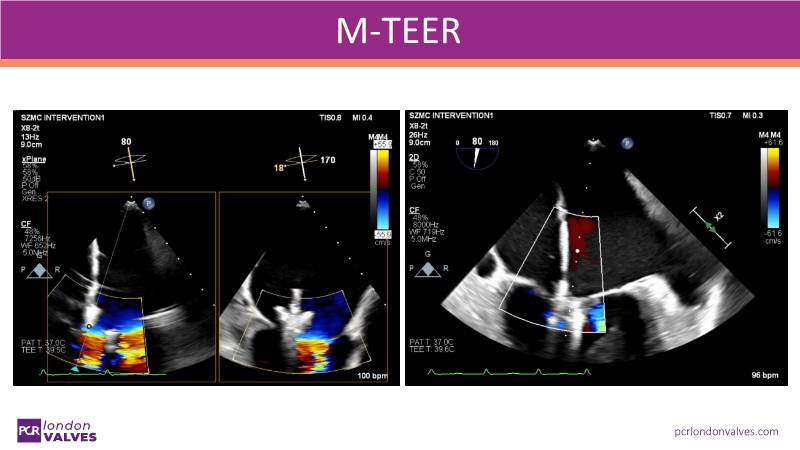

Mitral regurgitation: from guidelines to clinical practice

This LIVE case symposium brings mitral regurgitation guidelines into real clinical practice. Through step-by-step patient demonstrations and insightful discussion, the session explores how recommendations guide decision-making in ventricular and atrial secondary MR, how the heart team tailors therapy to individual anatomy and comorbidities, and how device iterations and procedural workflow can influence outcomes.